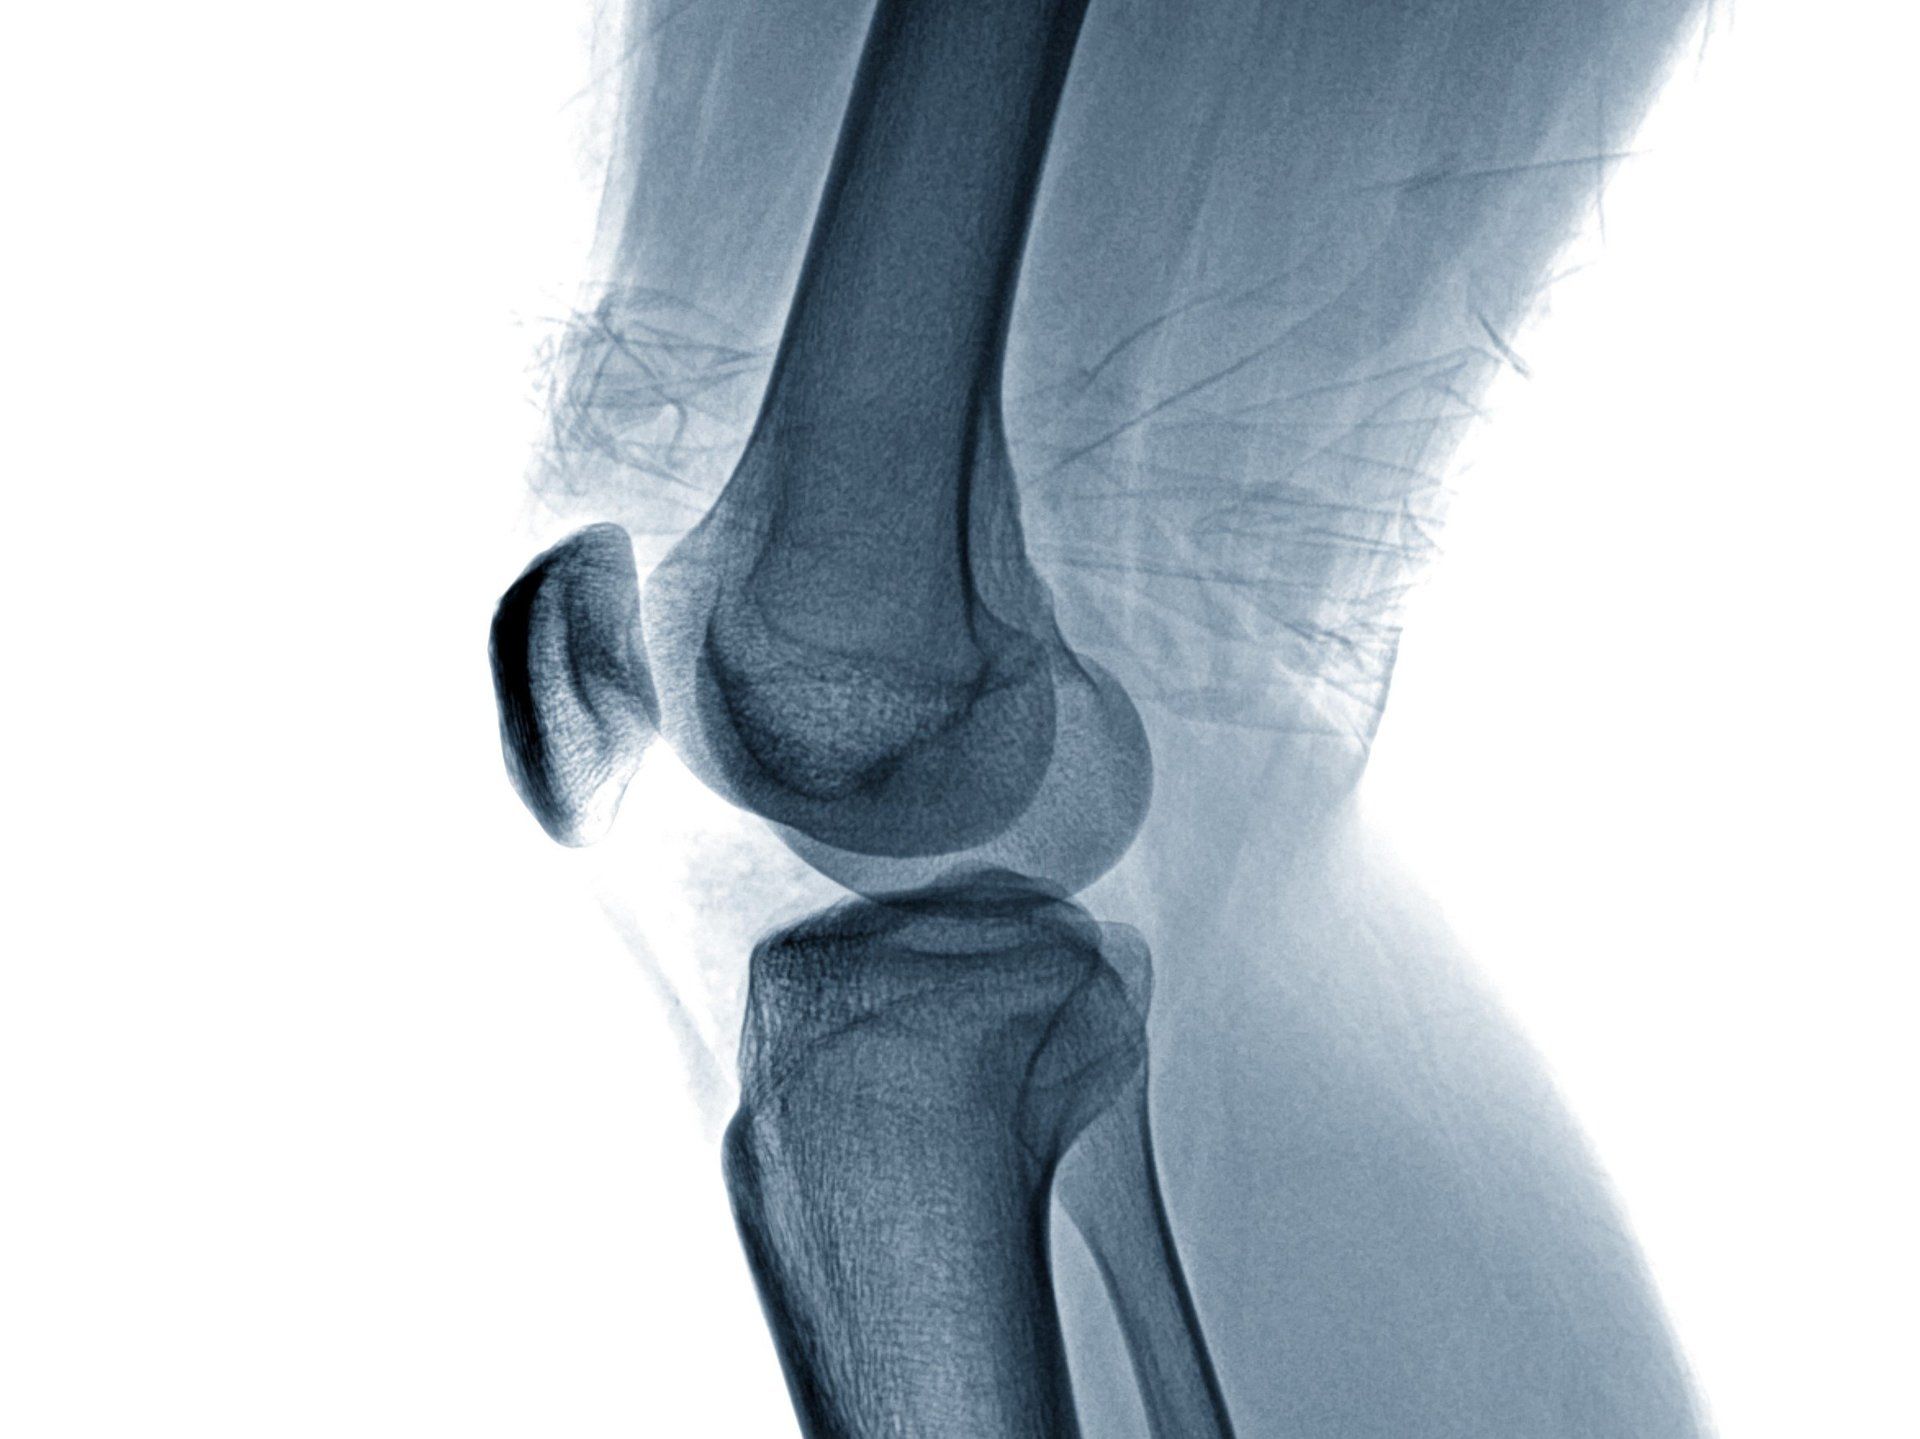

Arthrosebehandlung

Arthrose bezeichnet einen Erkrankungsprozess in den Gelenken bei dem die Knorpelschicht degenerativ verändert ist.

Die Arthrose geht oft mit einer sehr schmerzhaften Bewegungseinschränkung des betroffenen Gelenks einher.